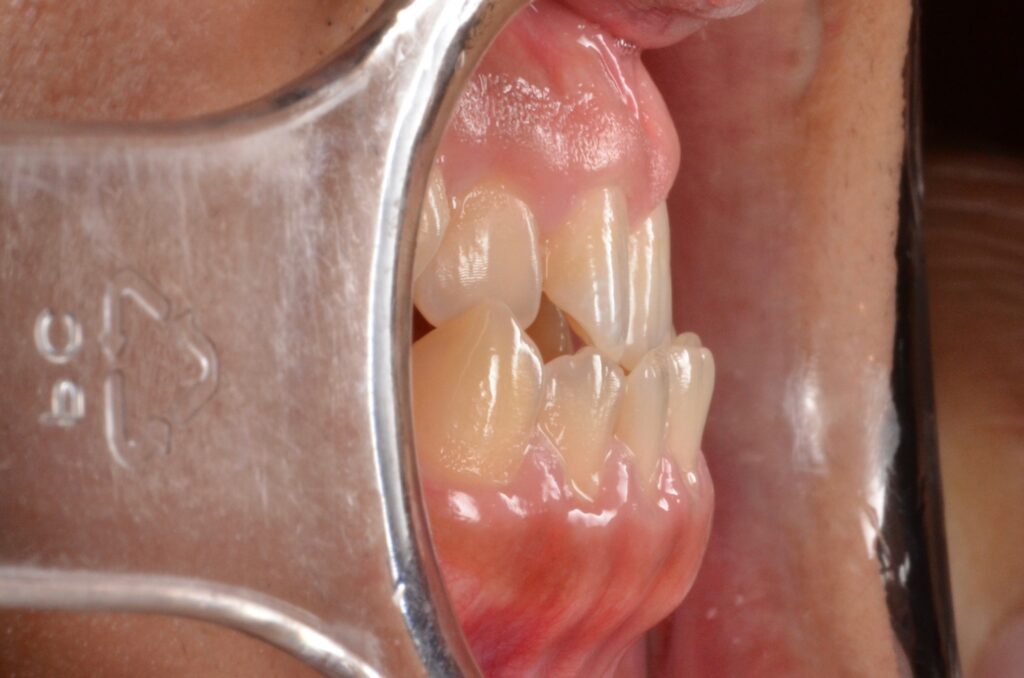

大学病院で顎の手術が必要と診断された20代男性の受け口を、ワイヤー矯正のみで治療した症例です。外科手術や抜歯は行わず、2年間かけて反対咬合を改善。事前の精密な診断が、的確な判断へと導きました。

| リスク・副作用 | リテーナーの不使用による矯正治療の後戻り |

|---|---|

| 費用 | 約125万円 (税別) |

| 期間 | 2年 |